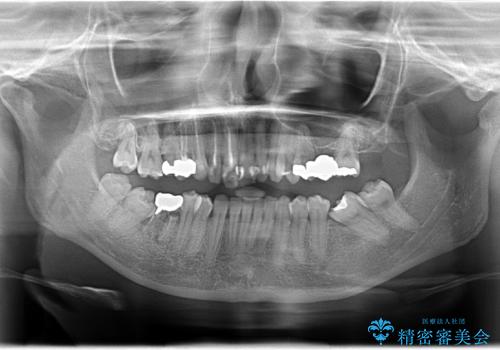

歯並びの改善とインプラントでのかみ合わせの回復 インプラント・セラミック・矯正全顎治療

- 歯医者が怖くて悪い歯をそのままにしてしまった、悪いところを治したいとのことで来院されました。

虫歯の歯や、歯を抜いてしまったところをそのまま放置していたことにより、歯並びも悪くなっていました。

矯正をはじめ、根の治療・インプラント・セラミックによる全体治療を提案させていただき、治療をしていくこととなりました。